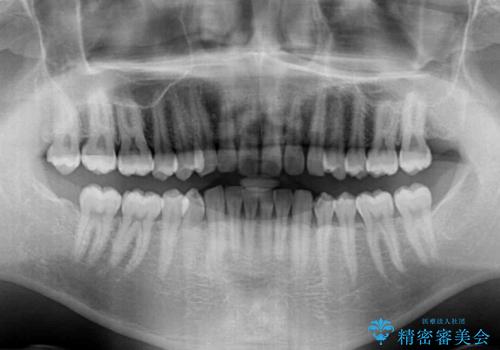

細かい隙間にものがはさまる インビザラインによる矯正治療

- 上下の前歯の隙間を気にして来院された患者様です。

インビザラインを用い、上下歯列のスペースを閉じていくこととしました。